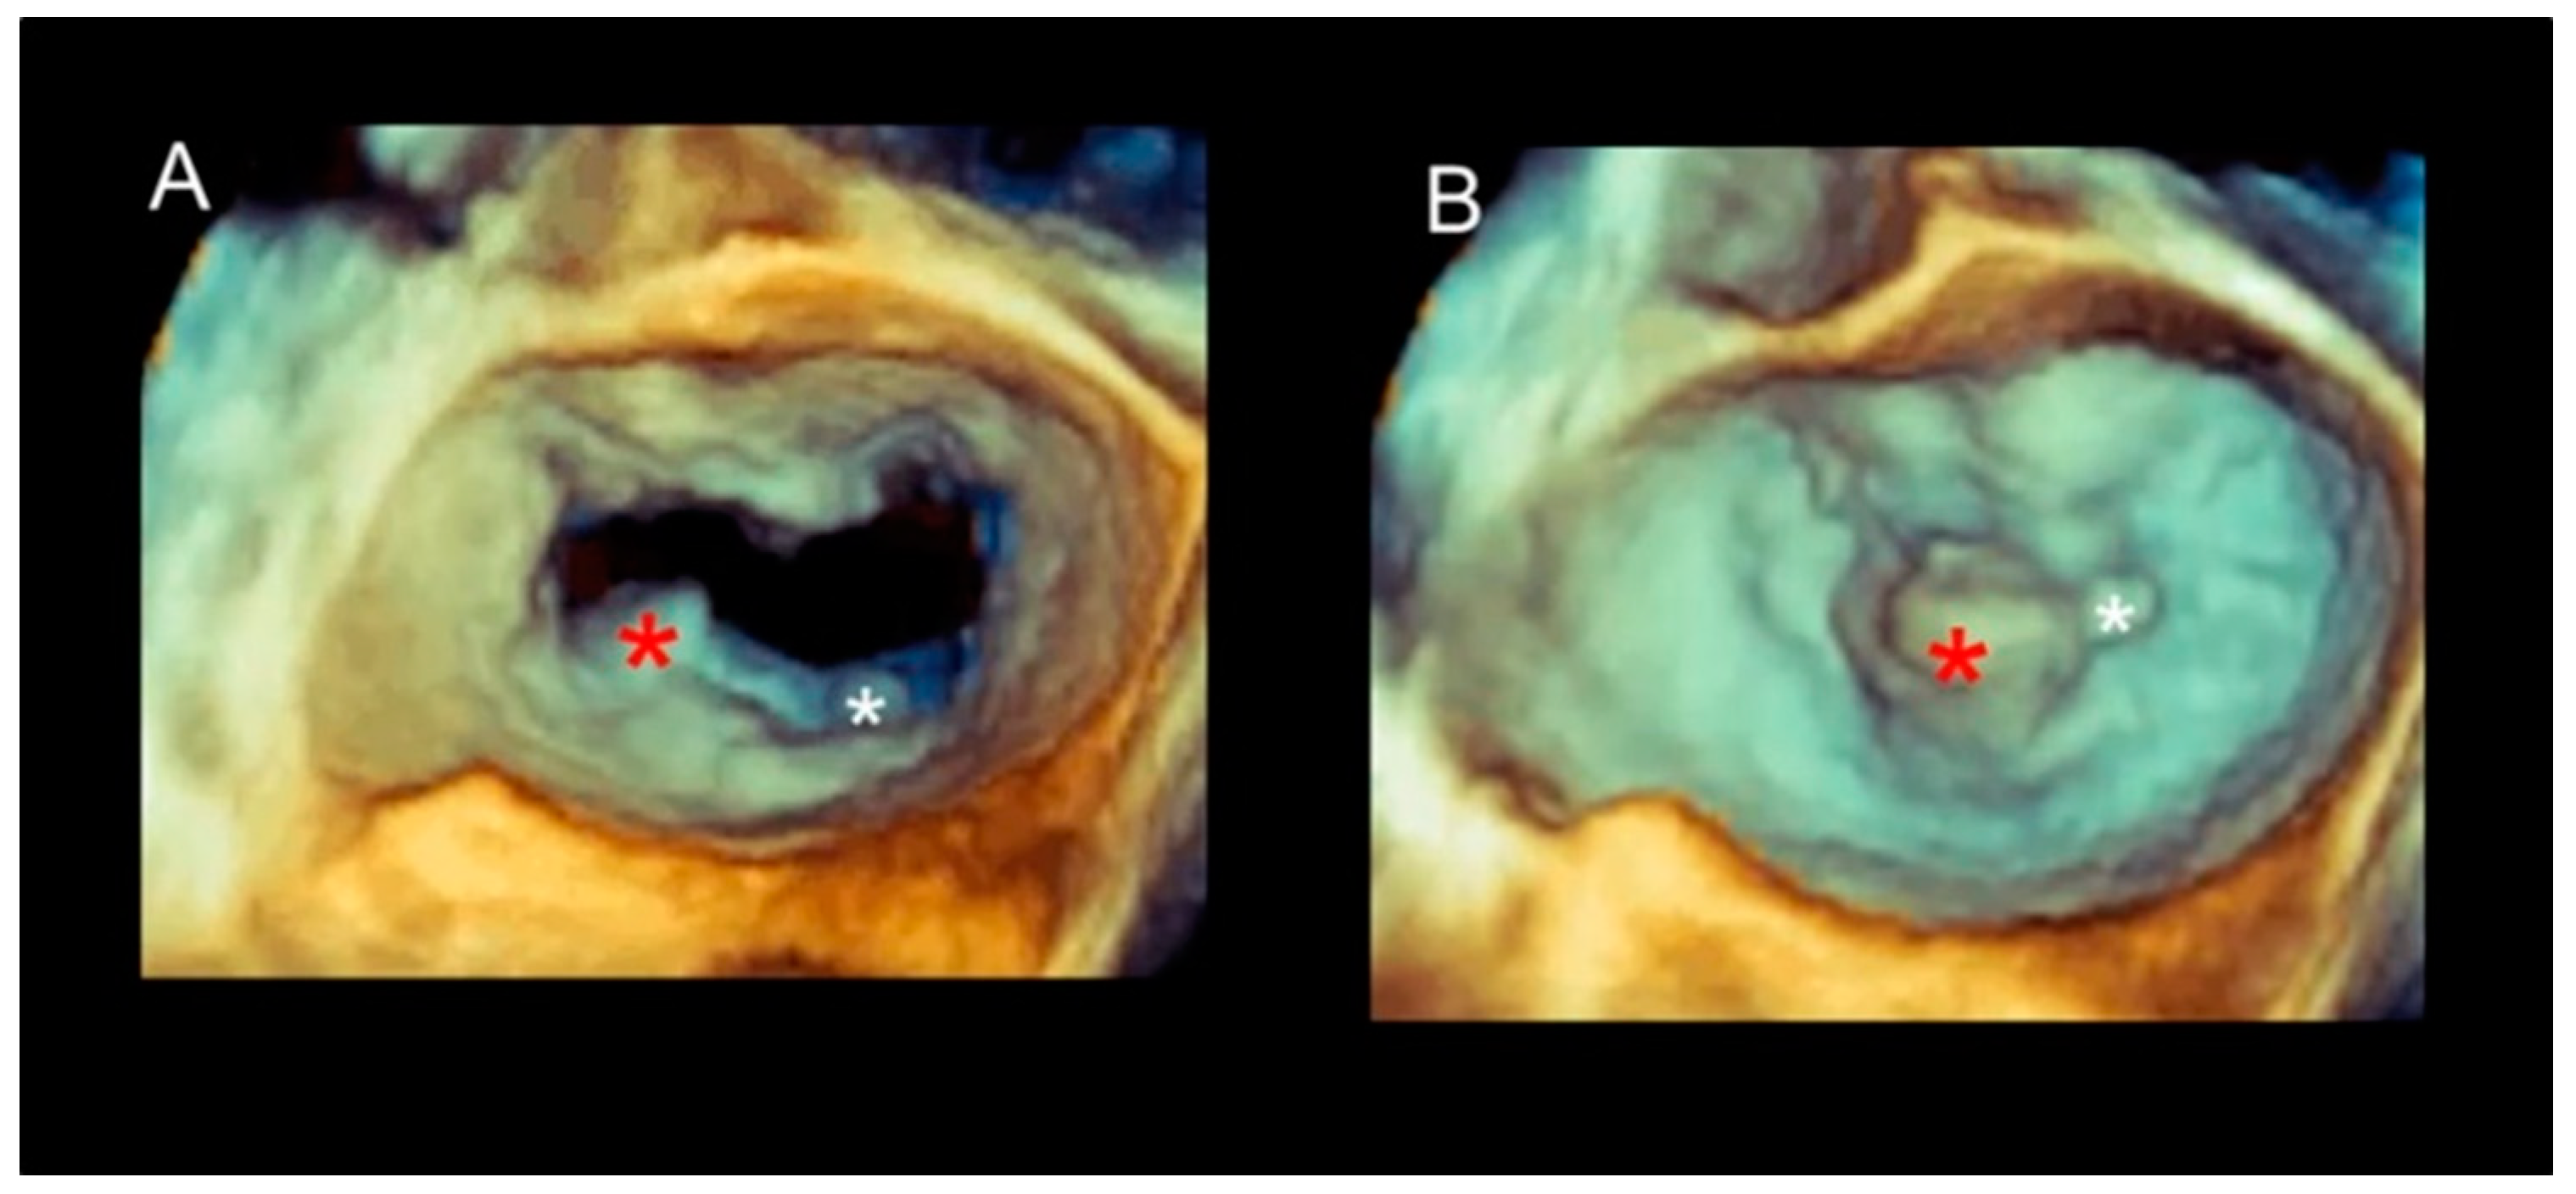

Cleft and Cleft-like Indentations

| Phenotype | Description | Image |

|---|---|---|

| Fibroelastic deficiency | This phenotype is characterized by a deficient production of collagen, elastin, and proteoglycans. Leaflets preserve their own three-layer arrangement, but upon surgical inspection, they appear fragile and translucent. The etiology of connective tissue deficiency in FED is unknown, but it has been suggested that it may be the result of an accelerated ageing process. The cause of regurgitation is the rupture of one or more primary chordae tendineae, which usually involves a single scallop. The figure shows a small P2 prolapse in an otherwise apparently normal MV. |  |

| Fibroelastic deficiency plus | This phenotype is characterized by a single scallop prolapse, but the involved scallop is redundant and affected by myxomatous degeneration. The remaining scallops are normal. Qualitative histological lesions in the prolapsed tissue of FED plus are similar to those of Barlow’s disease. It has been suggested that FED plus may be considered a sort of worsening stage of FED, leading to the hypothesis that the myxomatous changes could also be secondary to jet lesions. The figure shows a large P2 prolapse with ruptured chordae tendineae (arrows). |  |

| Forme fruste | In this phenotype, the entire posterior leaflet is redundant and is affected by myxomatous degeneration, while the anterior leaflet is macroscopically and histologically normal. It can be speculated that this phenotype is an incomplete form of Barlow’s disease. The figure shows multiple prolapses (asterisks) of the posterior leaflet. |  |

| Barlow’s disease | Barlow’s disease is the result of an abnormal accumulation of myxomatous substances (mainly proteoglycans) in the spongiosa layer, and a simultaneous disruption of collagen fibers in the fibrosa layer. As a consequence, the three-layered arrangement of the leaflets is lost. The characteristic macroscopic appearance, either in pathological specimens or in the operating room, is that of a thick, bulky, redundant leaflet, elongated chordae tendineae, and annular dilatation. The excess leaflet tissue leads to the displacement of both leaflets beyond the annulus, with a lack of coaptation and consequent MR. The figure shows an example of Barlow’s disease seen from a tangential view largely protruding into the left atrium. LAA = left atrial appendage, AML = anterior mitral leaflet; PML = posterior mitral leaflet. |  |